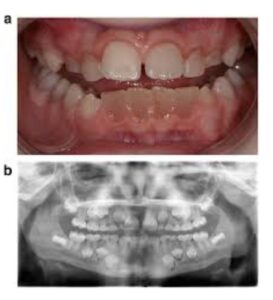

Lokal faktörlere bağlı oluşan renklenmelerin nedenleriyse şunlardır: Travma, pulpa nekrozu ve kalsifik metamorfoz.

Şekil 3 Kalsifik metamorfoz